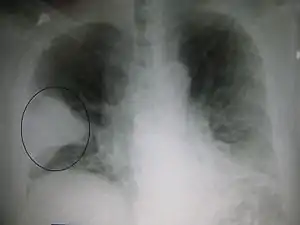

Gallery

Chest film showing increased opacity in both lungs, indicative of pneumonia